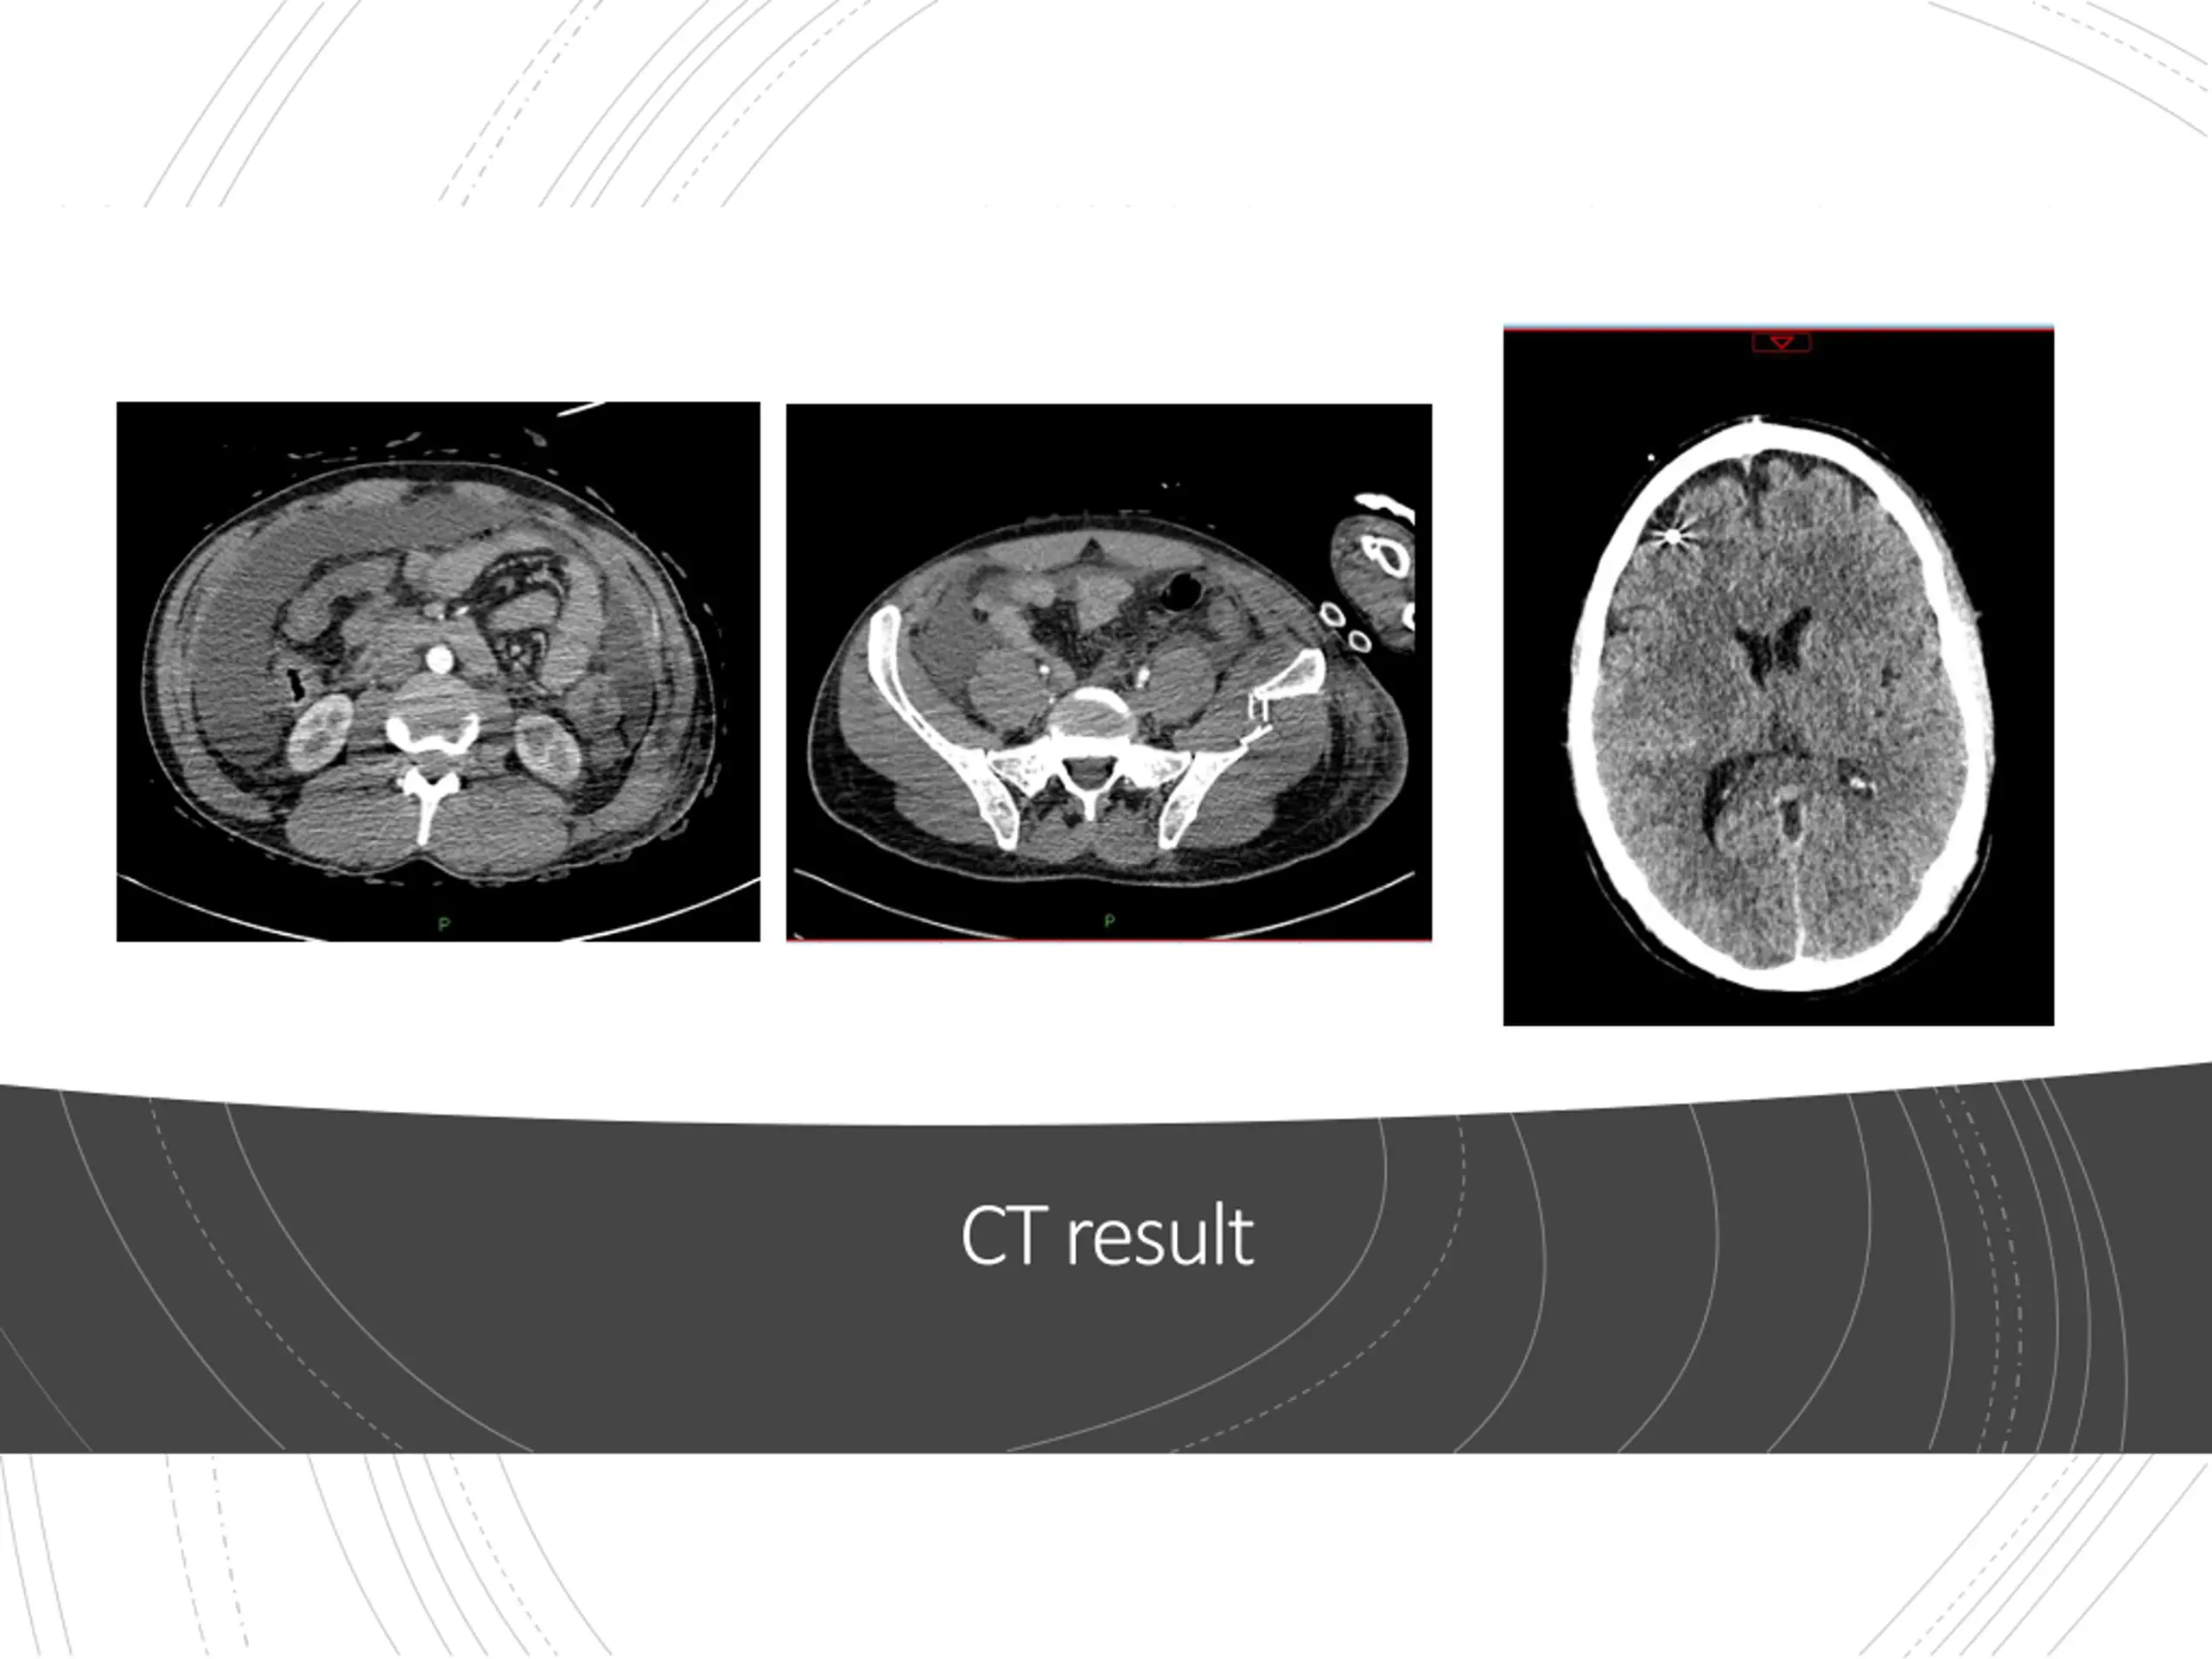

Admission to Intensive Care Neurocritical care Intracrainial Pressure monitor Sedated and ventilated Increasingly unstable CT Scan

Intensive Care Theatre Repair of small bowel perforation Returned to ICU 24hrs to stabilise, reducing organ support Extubated Discharged from ICU to Major Trauma Ward